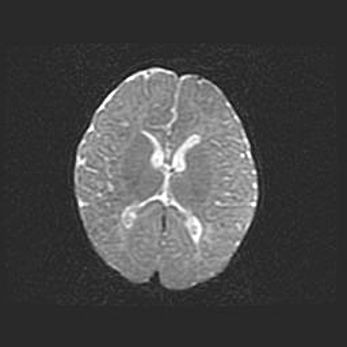

Множественные мелкие кисты перивентрикулярной области.

Киста прозрачной перегородки.

Возраст: 28 дней

Вес: 2400 г

Пол: женский

Окружность головы: 33 см

Срок гестации: 34 недели

Перивентрикулярная киста – это полостное образование в околожелудочковых областях белового вещества головного мозга. С морфологической точки зрения – это мелкоочаговая зона коагуляционного некроза, возникшая после инфаркта белого вещества. Наиболее часто поражаются начальные отделы задних рогов боковых желудочков. Обычно образования заполнены жидкостным содержимым.

Киста прозрачной перегородки может располагаться в переднем отделе межжелудочковой перегородки, в области мозолистого тела и мозжечка.